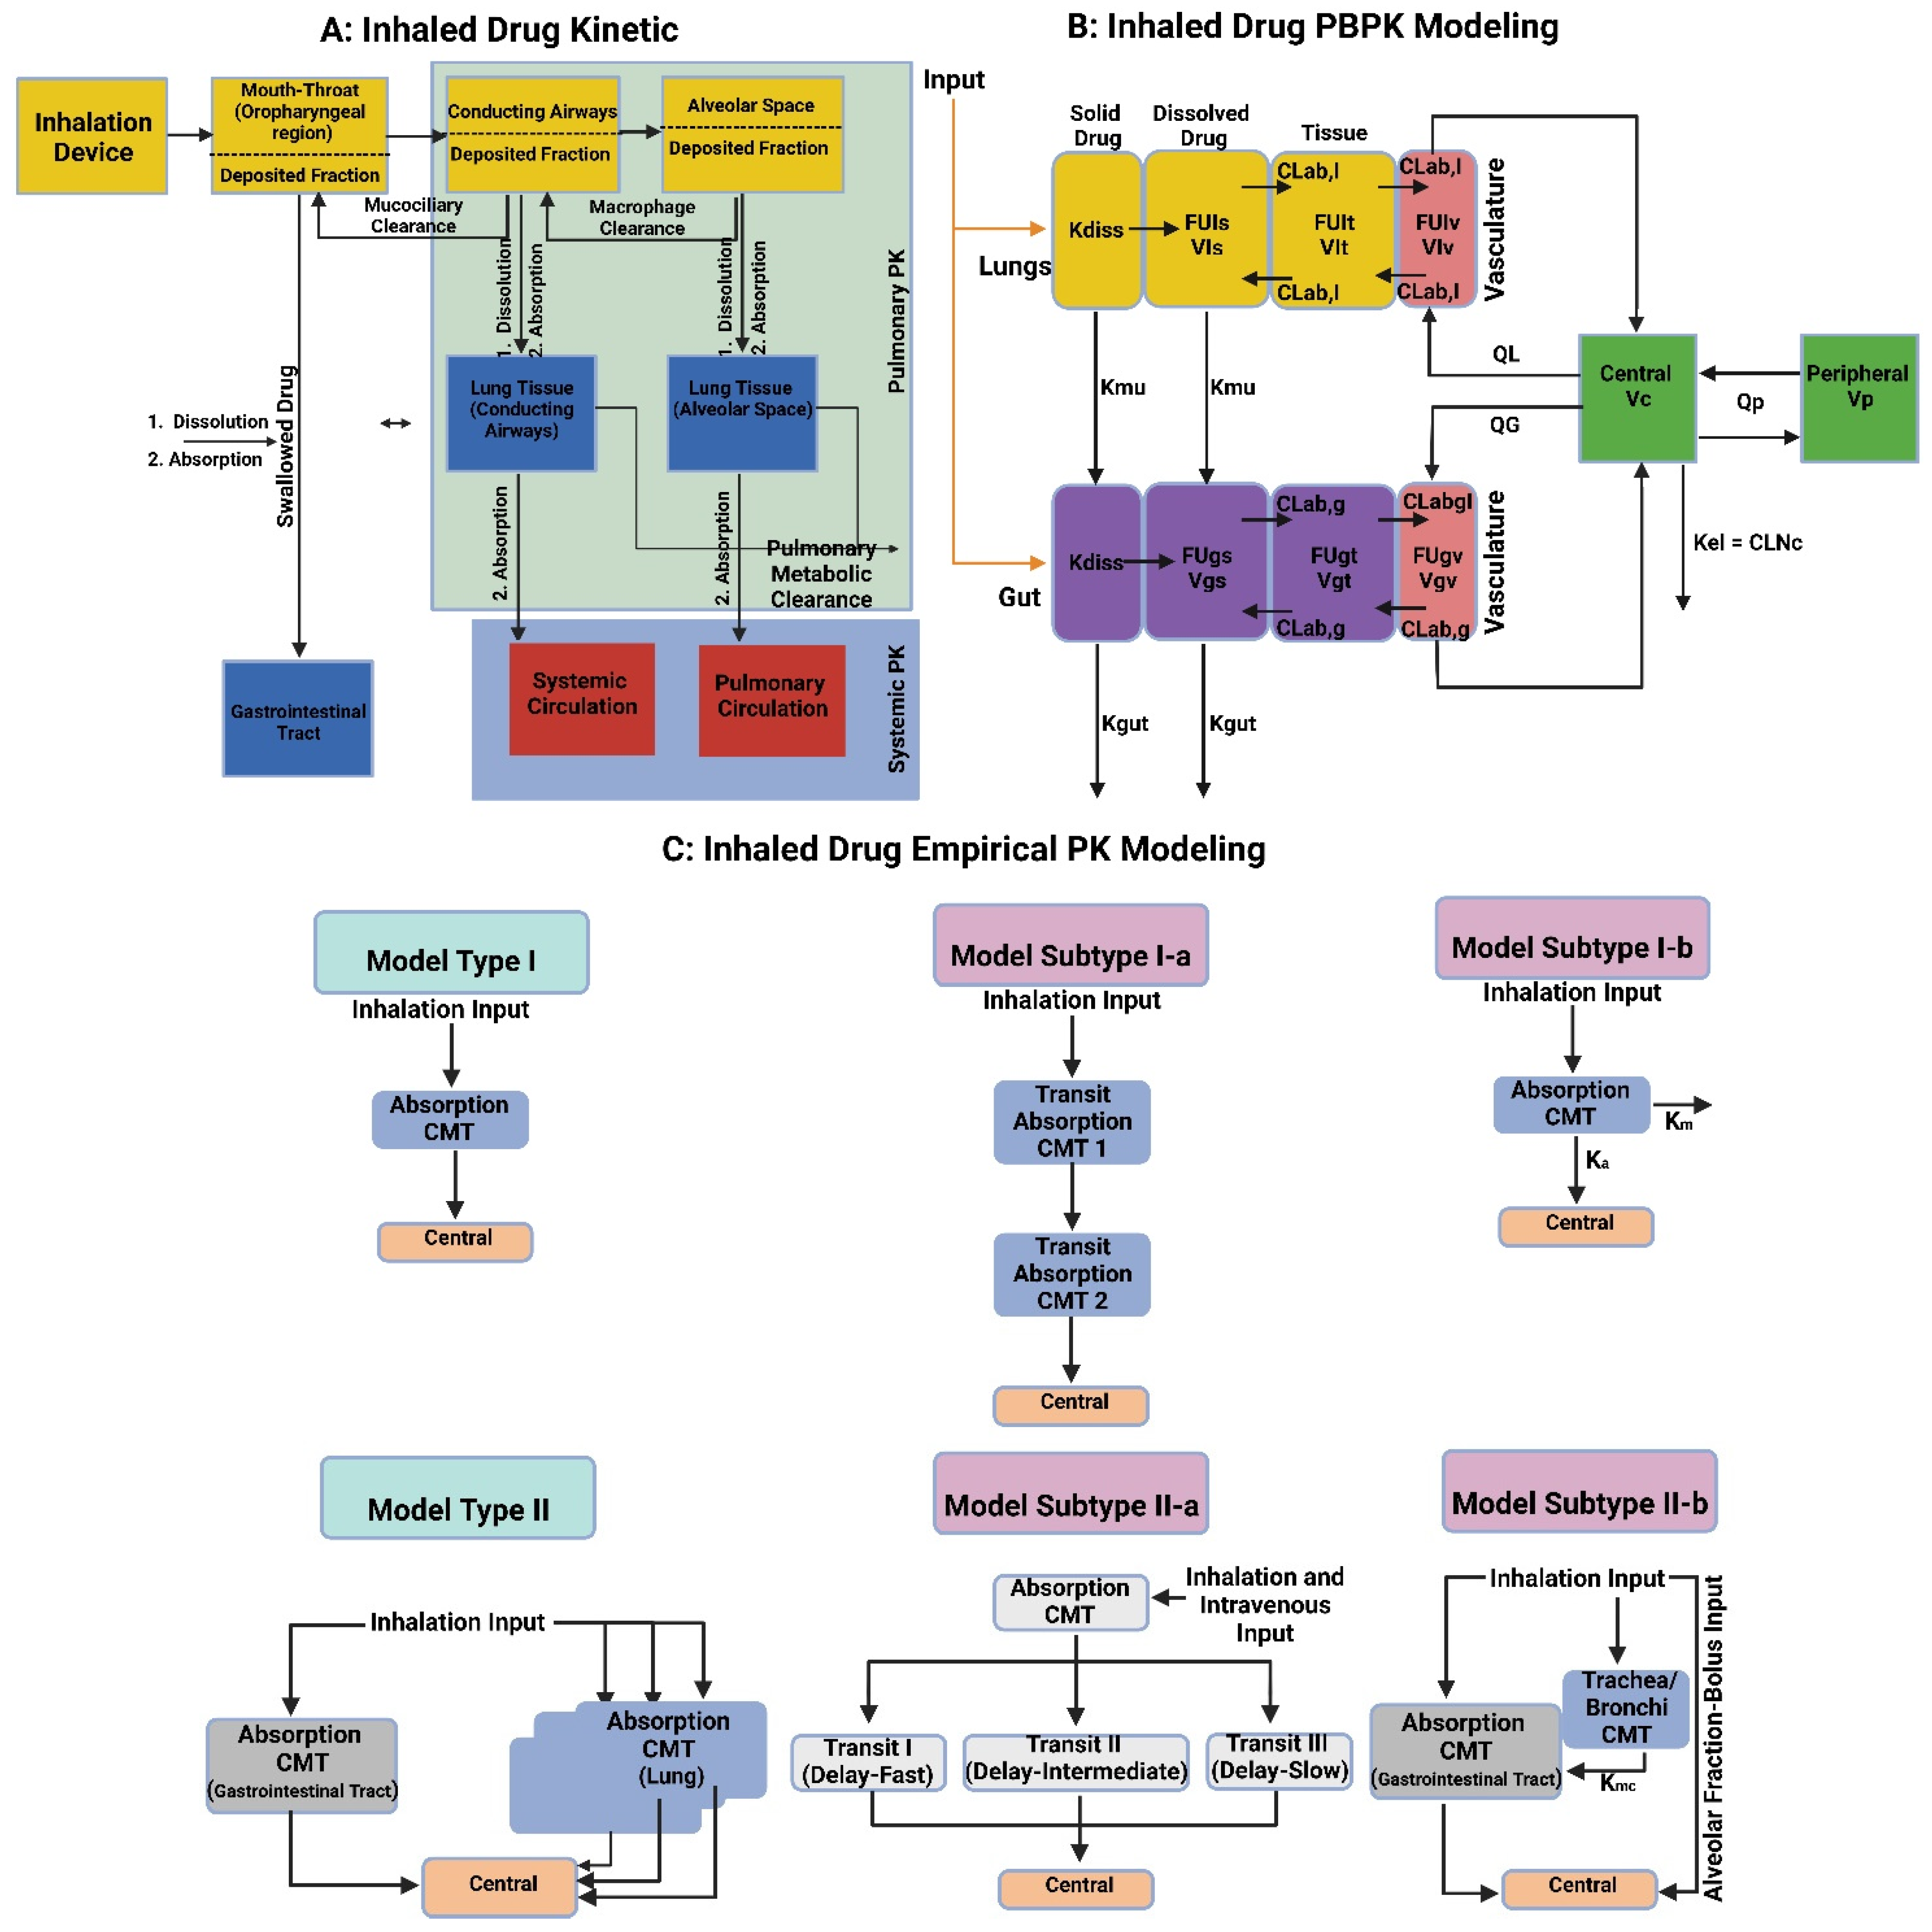

8.1. Pharmacological/PKPD Challenges